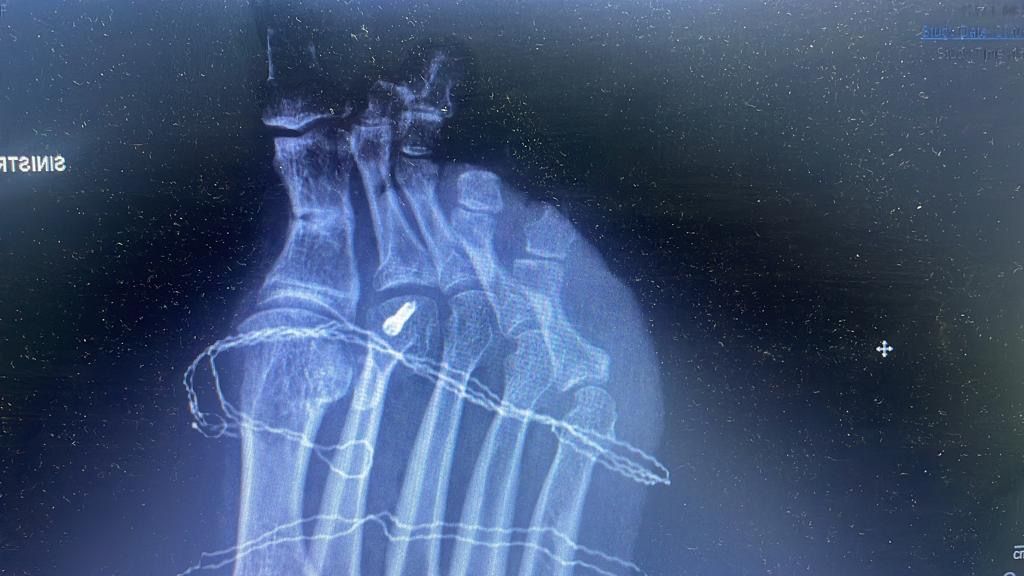

Esistono numerose tecniche chirurgiche, attualmente la più accreditata è l’intervento mini invasivo S.E.R.I. che prevede la correzione dell’osso mediante il posizionamento di un filo, che verrà rimosso a guarigione avvenuta.